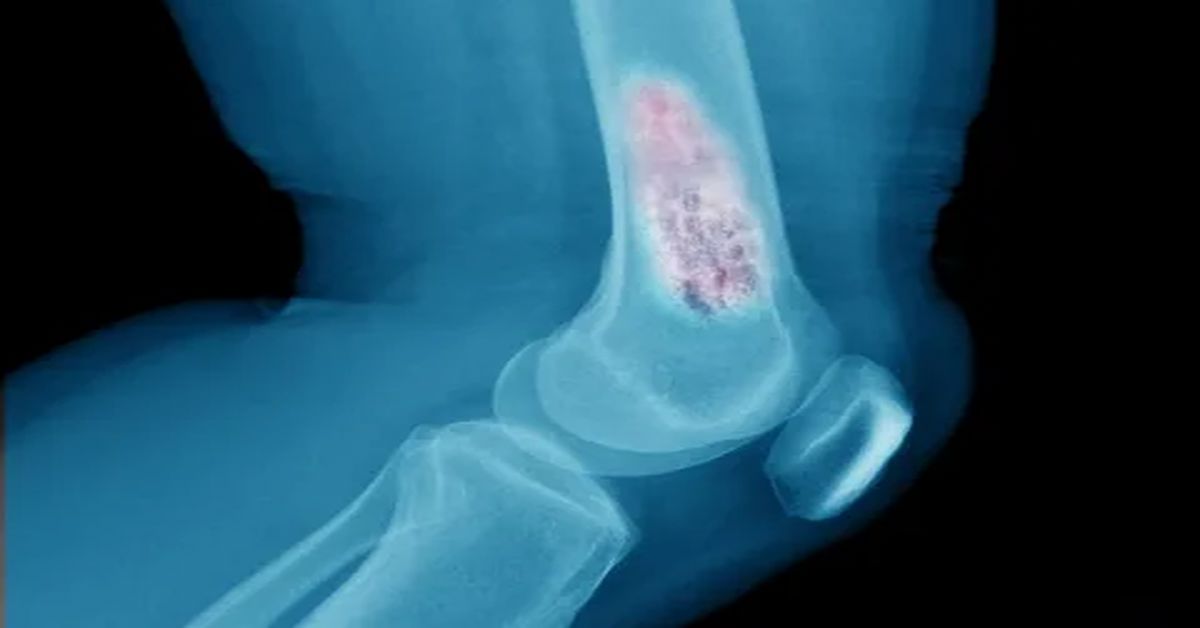

Kas, yağ, sinir, bağ dokusu gibi yumuşak dokularda oluşan anormal hücre büyümesidir. Yumuşak doku tümörü, iyi huylu ya da kötü huylu olabilir. Genellikle ağrısızdır. Şişlik şeklinde fark edilir. Büyüklüğü zamanla artabilir. Tanı için görüntüleme ve biyopsi gerekir. Tedavi cerrahi, kemoterapi veya radyoterapi ile yapılabilir. Erken teşhis önemlidir.

Yumuşak doku tümörleri, kas, yağ ve bağ dokusunda gelişebilen oluşumlardır. Bu tümörler iyi huylu ya da kötü huylu olabilir. Genellikle yavaş büyür ve erken dönemde fark edilmeyebilir. Vücudun farklı bölgelerinde ortaya çıkabilir. En sık kol ve bacaklarda görülür. Erken teşhis, tedavi sürecini olumlu etkiler.

Yumuşak doku tümörlerinde tedavi planı hastanın genel durumuna göre belirlenir. Tümörün yeri, boyutu ve türü bu süreçte önemlidir. İlk aşamada detaylı muayene yapılır. Gerekli durumlarda görüntüleme yöntemleri kullanılır. Bu sayede tümörün yapısı net olarak değerlendirilir. Erken tanı tedavi sürecini kolaylaştırır.